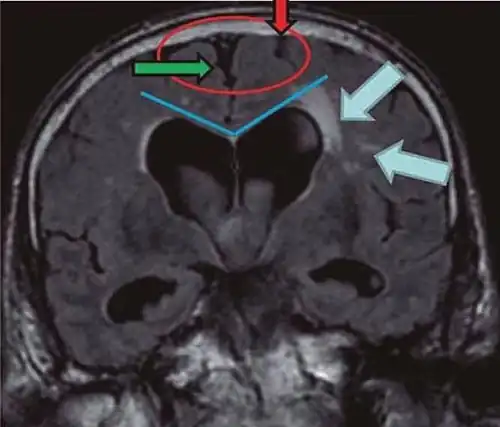

- Imaging from magnetic resonance imaging (MRI) or computed tomography (CT) is needed to demonstrate enlarged ventricles and no macroscopic obstruction to cerebrospinal fluid flow. Imaging should show an enlargement to at least one of the temporal horns of lateral ventricles, and impingement against the falx cerebri resulting in a callosal angle ≤ 90° on the coronal view, showing evidence of altered brain water content, or normal active flow (which is referred to as "flow void") at the cerebral aqueduct and fourth ventricle.

| Normal pressure hydrocephalus | Brain atrophy | |

|---|---|---|

| Preferable projection | Coronal plane at the level of the posterior commissure of the brain. | |

| Modality in this example | CT | MRI |

| CSF spaces over the convexity near the vertex (red ellipse |

Narrowed convexity ("tight convexity") as well as medial cisterns | Widened vertex (red arrow) and medial cisterns (green arrow) |

| Callosal angle (blue V) | Acute angle | Obtuse angle |

| Most likely cause of leucoaraiosis (periventricular signal alterations, blue arrows |

Transependymal cerebrospinal fluid diapedesis | Vascular encephalopathy, in this case suggested by unilateral occurrence |

MRI scans are the preferred imaging. The distinction between normal and enlarged ventricular size by cerebral atrophy is difficult to ascertain. Up to 80% of cases are unrecognized and untreated due to difficulty of diagnosis.[22] Imaging should also reveal the absence of any cerebral mass lesions or any signs of obstructions. Although all patients with NPH have enlarged ventricles, not all elderly patients with enlarged ventricles have primary NPH. Cerebral atrophy can cause enlarged ventricles, as well, and is referred to as hydrocephalus ex vacuo. For these reasons it's utmost important to note that Evan's index although commonly used in imaging is not very specific for NPH. One recent systematic review and meta-analysis suggests that callosal angle has high diagnostic performance and is commonly used together with Evan's index.[23]